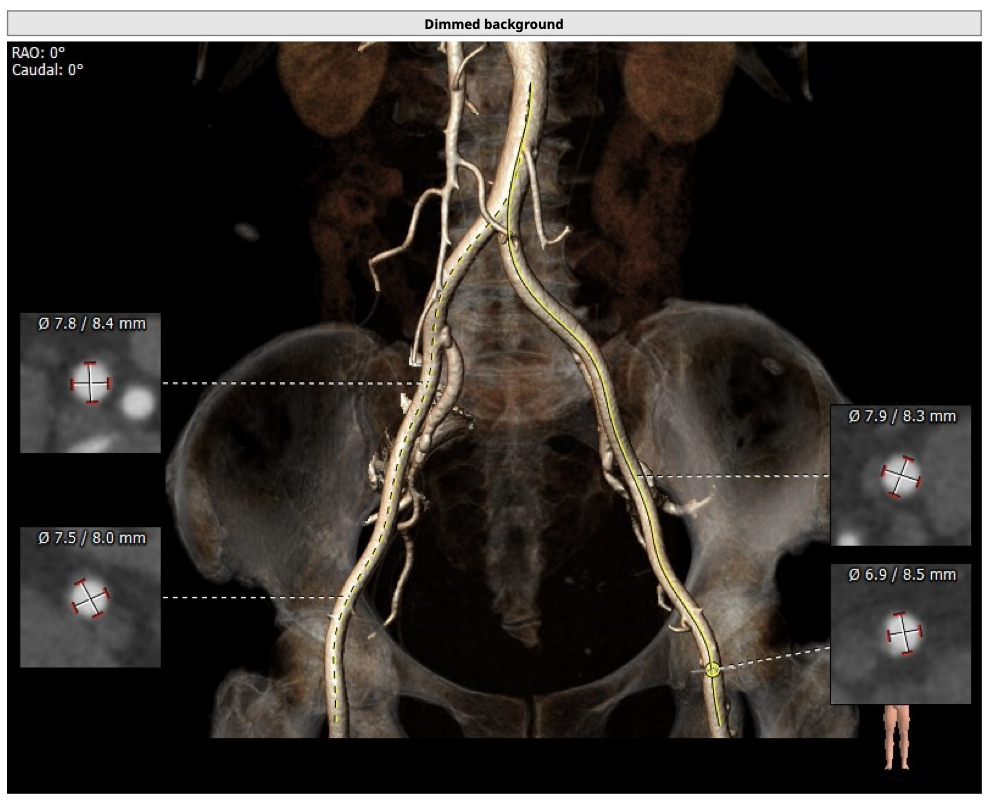

主动脉CT

患者为TYPE0型二叶瓣,轻中度钙化,瓣叶可见增厚,冠脉高度可,法式窦结构大,左室大小尚可,心肌肥厚,升主动脉可见增宽。

经分析研判,结合患者瓣上结构,拟采取downsize手术策略,优先选用L26号的VenusA-Valve瓣膜,备L23,使用VenusA-Plus确保瓣膜的精确释放,减少瓣膜移位风险,瓣膜释放后结合造影和超声情况,决定是否后扩。